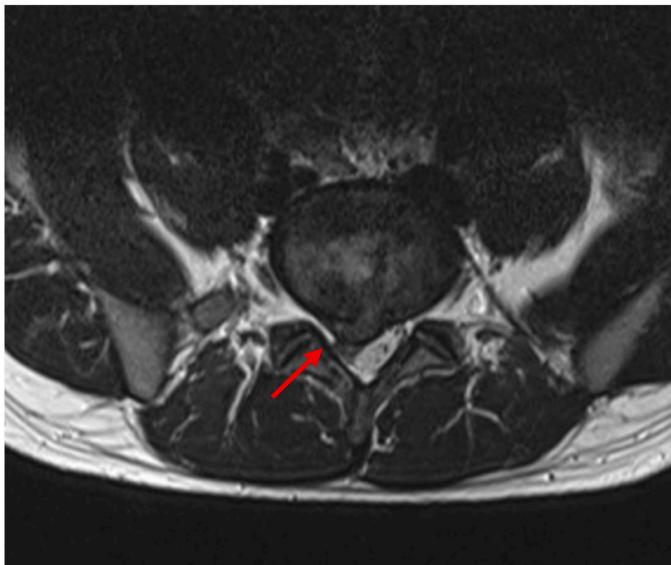

L5/S1 Disc Herniation Example: